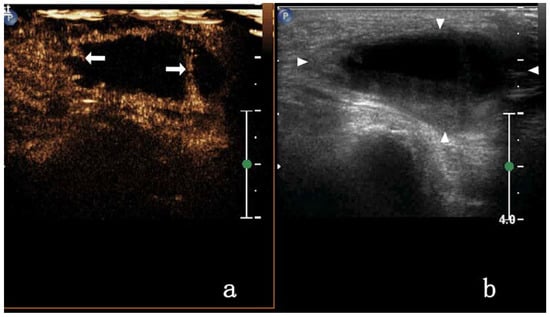

| CEUS degree | 18.865 | 0.000 | |||

| Homogeneous enhancement | 3/17 (17.64%) | 23/28 (82.14%) | |||

| Heterogeneous enhancement | septal enhancement | 4/17 (23.52%) | 0 | ||

| Annular enhancement | 4/17 (23.52%) | 5/28 (17.85%) | |||

| Nodule-in-nodule enhancement | 3/17 (17.64%) | 0 | |||

| non-enhancement | 3/17 (17.64%) | 0 | |||

| Enhanced intensity | 17.455 | 0.000 | |||

| Low enhancement | 5/17 (29.41%) | 0 | |||

| Equal enhancement | 4/17 (23.52%) | 0 | |||

| High enhancement | 8/17 (47.05%) | 28/28 (100%) | |||

| CEUS mode | 15.074 | 0.000 | |||

| Centripetal enhancement | 0 | 16/28 (57.14%) | |||

| Noncentripetal enhancement | 17/17 (100%) | 12/28 (42.85%) | |||